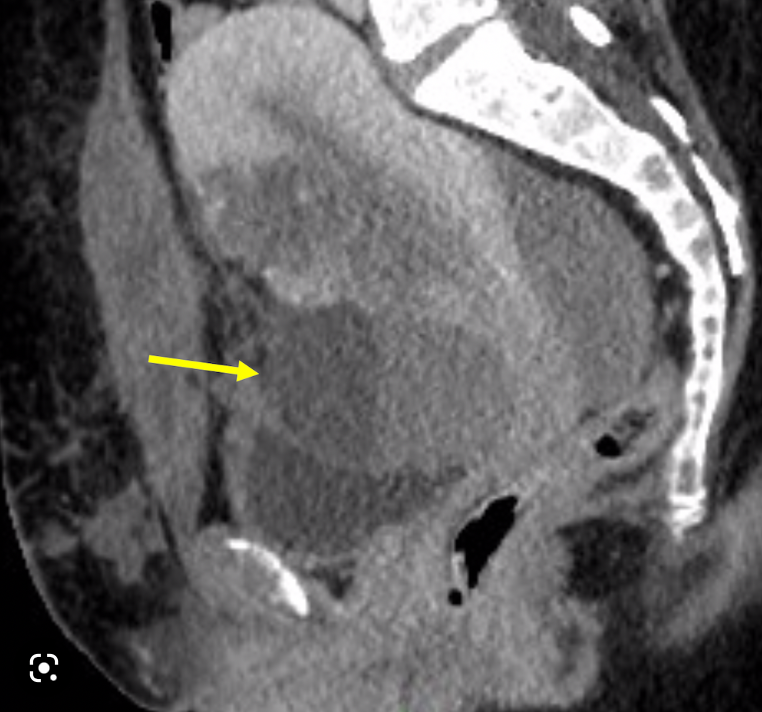

16

Q

40 y/o F

A

Think bladder leiomyoma

Note: Smooth, solid, homogenous soft tissue mass in the region of the trigone (most common location).